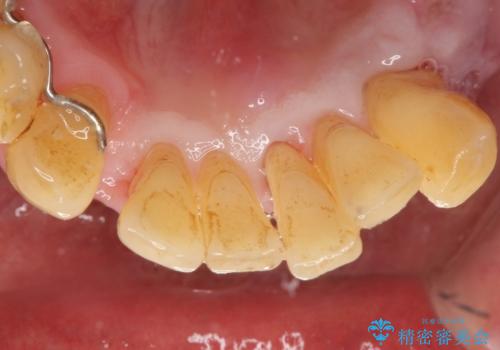

精査したところ、全顎的な重度の歯周病により下顎前歯に激しい動揺を認めました。

歯も神経も残したいという患者様のご希望により、補綴前に部分矯正を行っております。

- ¥1,342,000 (再生療法、骨外科処置、部分矯正、仮歯×6本、クラウン×6本) ※税込費用は治療当時の料金となります